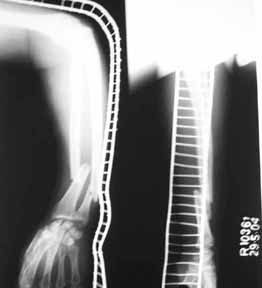

Middle aged adult hospital employee invoved in a road traffic accident. Suffered closed hip dislocation left side and fracture both bones right forearm(ulna compound) Underwent closed reduction of right hip and debridement with ORIF of forearm. Pre op X-ray showed acetabular rim fracture and post op X-ray showed a suspicious fracture line through the head of femur. One fragment of acetabulum seen displaced. CT done subsequently shows an undisplaced fracture through the head of femur with the acetabular rim fracture which is displaced.